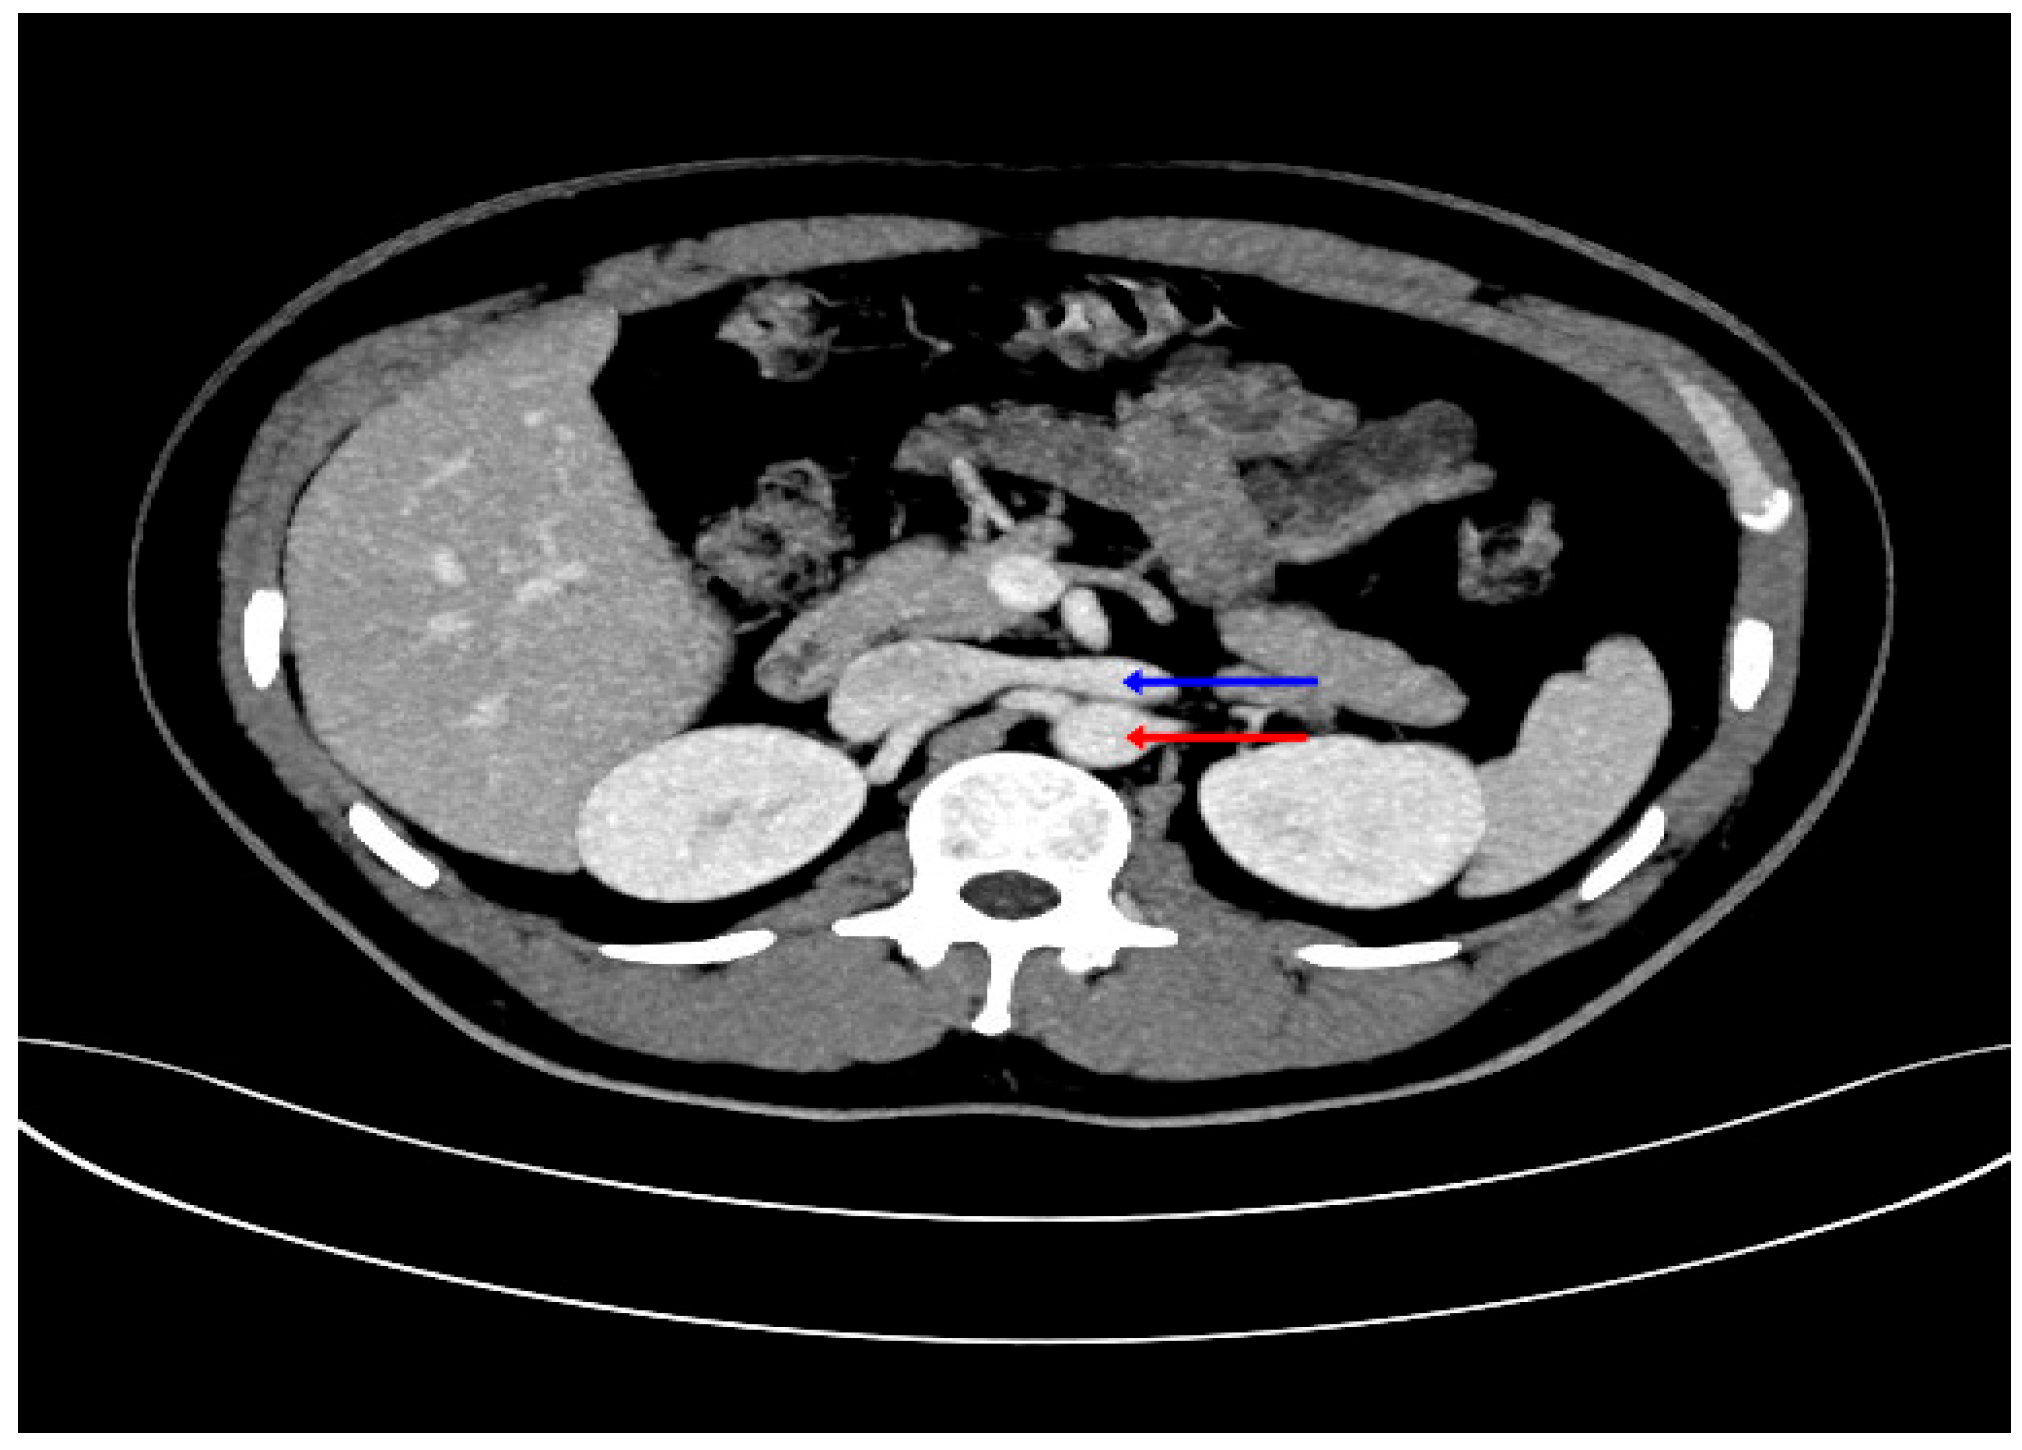

| Single left RV, anterior to aorta | 88 | 32 | 120 |

| Circumaortic with both trunks | 1 | - | 1 |

| Retroaortic | 3 | 4 | 7 |